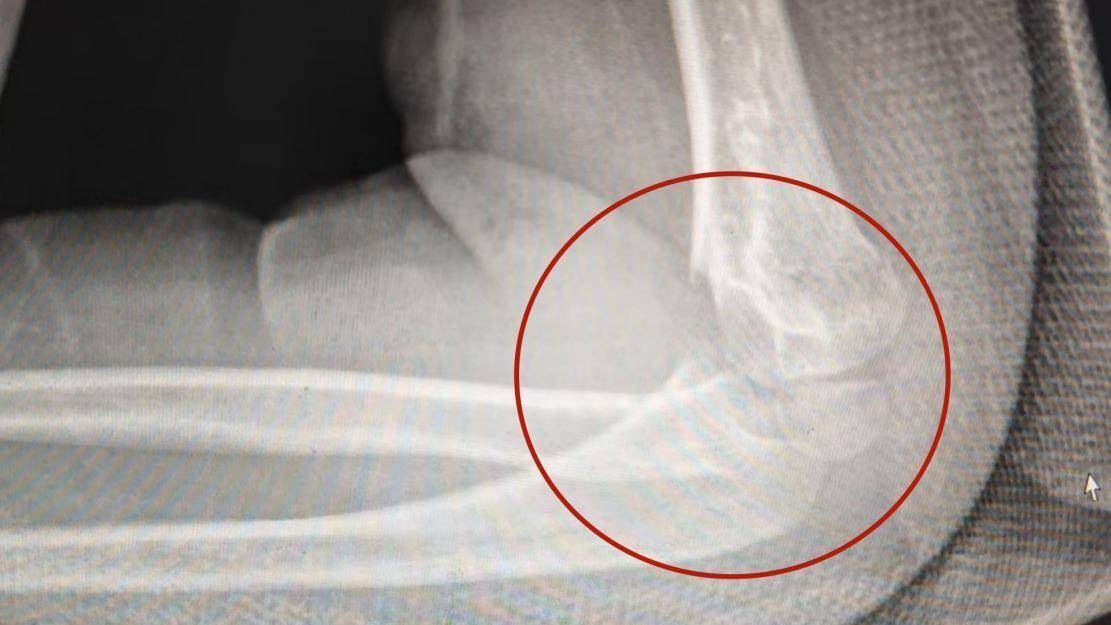

患者手臂骨折部位。康复介入:调和“养伤”与“防僵”之间的矛盾,安全“解冻”“‘养伤’需固定,‘防僵’要活动,这对矛盾要靠康复医学调和,且是与时间的较量。”康复医学科副主任、副主任医师王井泉介绍,介入时机至关重要,既要保障损伤结构安全愈合,又要尽早恢复关节活动功能。基于此,康复医学科骨关节小组为李远制定综合方案:先专业评估,确保骨折部位稳定,避免二次伤害;评估达标后,运用关节松动术等手法松解粘连组织,同步开展科学、安全的功能锻炼,指导患儿及家属执行;必要时采用“石膏开窗”策略,在确保骨折固定前提下,阶段性开窗训练,打破制动枷锁,恢复活动能力。经过科学干预,李远肘关节功能奇迹般恢复,现已重返校园。破除误区:“伤筋动骨一百天”≠全程静卧王井泉提醒市民,肘关节损伤后要警惕误区:传统观念认为“伤筋动骨一百天”就全程静养不动,这极易酿成严重后果。专业数据显示,超过 6 周未进行专业康复干预的肘关节损伤,患者终生关节活动受限或致残风险将显著增高。若受伤后发现肘部皮肤皱纹消失(肿胀或粘连)、活动时关节内有“咯噔”弹响感、主动或被动活动范围明显减小,这是关节开始“冻结”的红色警报,过度静养是常见原因。王井泉表示,早期、科学、专业的康复介入,是避免肘关节永久冻结、最大限度恢复功能、重归正常生活的根本保障。任何肘关节损伤(如骨折、韧带问题),从治疗伊始就应融入康复理念,患者务必尽早前往正规医院康复医学科就诊。康复评估应从打上石膏第一天起介入并贯穿全程,专业康复医师会根据个体情况制定安全“解冻”方案,精准把握结构愈合与功能恢复的平衡点。举报/反馈